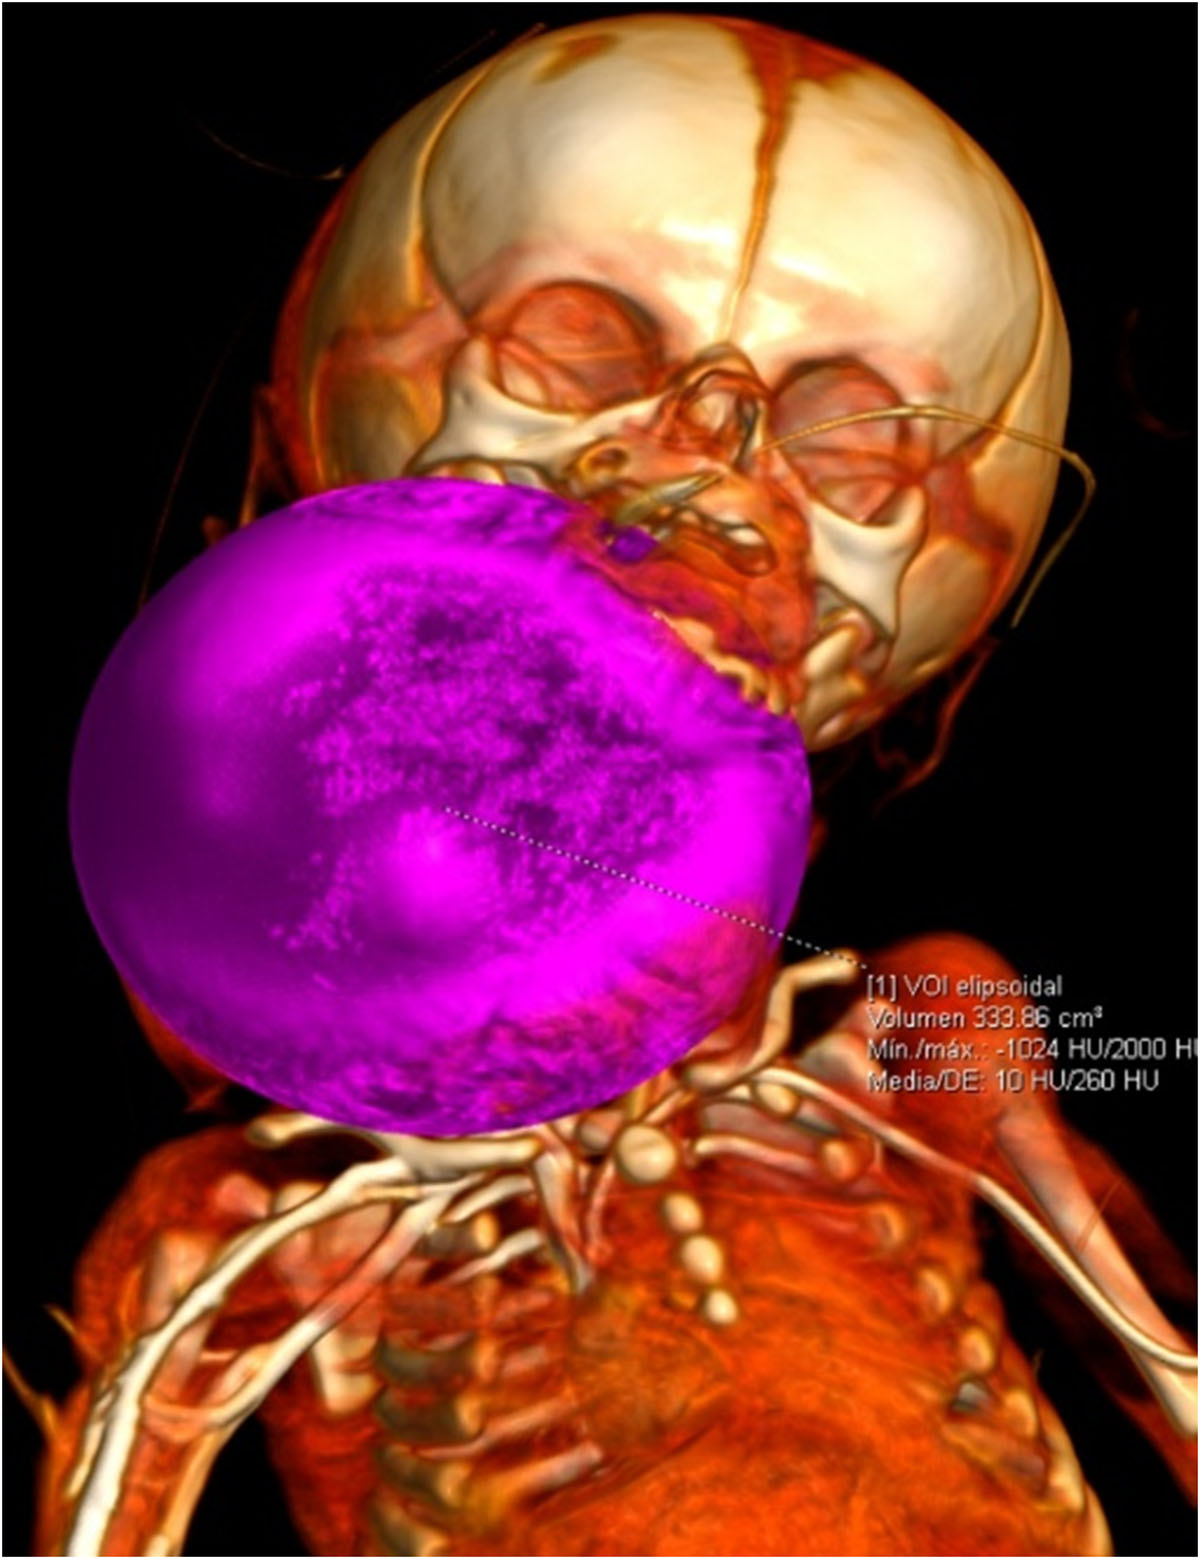

Se identifica imagen redondeada, de bordes lobulados, dependiente de tejidos blandos, heterogénea por áreas sólidas y quísticas internas, así como algunas calcificaciones irregulares dispersas, tras la aplicación de medio de contraste con realce ávido heterogéneo en sus porciones sólidas, con dimensiones de 89.3×88.3×80.9 mm y volumen de 333.6 cc; localizada en los espacios masticador, parotídeo, parafaríngeo, submandibular, visceral, supraesternal, perivertebral bucal y cervical posterior derechos.5. IMÁGENES

Se realiza cirugía el día 13/10/25 encontrando los siguientes hallazgos: Tumor cervical encapsulado de aproximadamente 30 x 45 cm de consistencia firme, no infiltrante, con desplazamiento pero sin invasión de estructuras adyacentes.

- Teratoma inmaduro en cuello

El teratoma cervical es una neoplasia congénita rara, derivada de células germinales pluripotenciales que contienen tejidos de las tres capas embrionarias. Representa menos del 5% de los teratomas pediátricos y su localización en el cuello puede ocasionar compromiso de la vía aérea, constituyendo una urgencia neonatal potencialmente mortal.